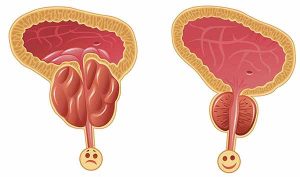

Prostat vəzinin quruluşu

Prostat vəzi –kiçik çanaqda, sidikliyin altında, sidik cinsiyyət diafraqmasının üzərində, qasıq bitişməsinin arxasında, düz bağırsağın önündə yerləşir və boz rəngdə olub sərt konsistensiyalıdır.

Prostat vəzinin çəkisi 20-25 q, köndələn ölçüsü 4 sm, boylama ölçüsü 3 sm, qalınlığı 2 sm qədərdir. Prostat vəzinin əsası sidikliyin yuxarı hissəsinə, zirvəsi isə sidik cinsiyyət diafraqmasına baxır. Prostat vəzinin ön və arxa səthləri vardır. Vəzin ön səthi qasıq bitişməsinə, arxa səthi düz bağırsaq ampuluna söykənir.

Prostat vəzinin adenoması nədir?

Prostat vəzinin adenoması — prostat vəzinin xoşxassəli şişidir. Buna görə də bu xəstəliyin digər rəsmi adı – prostat vəzinin xoşxassəli hiperplaziyası (boyüməsi). Prostat vəzinin adenoması kişilər arasında çox yayılmış xəstəlik olub, adətən, yaşı 40-dan yuxarı olan kişilərdə təsadüf edilir.